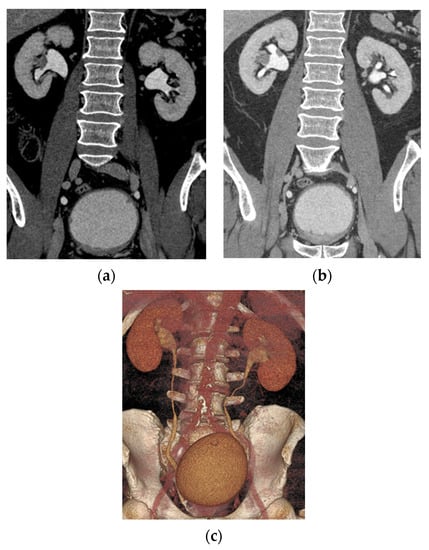

5.1. Computed Tomography (CT)